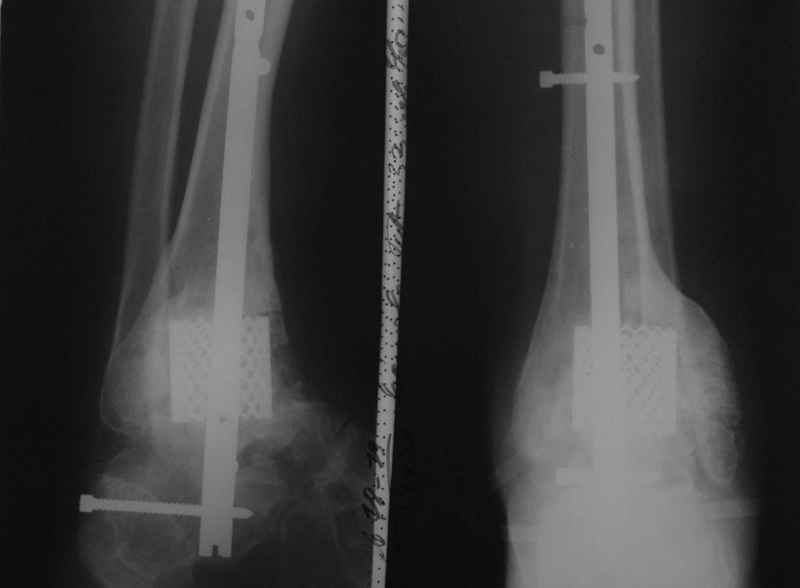

Пациентка Б. получила травму 2001 году в результате падения с высоты. За это время дважды выполнялись неудачные попытки артродезирования голеностопного сустава. Больная перед нами поставила одну задачу - восстановить опороспосонбность левой нижней конечности и только. Принято решение выполнить кейдж-артродезирование левого голеностопного сустава блокируемым интрамедуллярным гвоздем с установкой сетчатого опорного трансплантата, костной аутопластикой плюс Chronos. С целью профилактики рецидива деформации выполнили ахиллотомию (считаем, что неудачи предшествующих операций связаны с варусной тягой ахиллова сухожилия в ррезцльтате неправильно сросшегося перелома пяточной кости). На сегодняшний день - два месяца с момента операции. Пациентка перемещается в циркулярной повязке с полной нагрузкой на больную ногу.

Был использован металлокаркас производства МАТИ, разработанная методика коллективом ЦИТО во главе с А.Ф. Лазаревым, область -применения дефекты

длинных трубчатых костей, конечно не удаляется.

В данном случае мы столкнулись с проблемой мощного гиперпластического процесса в области голеностопного сустава, невозможностью или высокой

травматичность сближения артродезируемых оверхностей, поэтому решили применить кейдж из никилида титана и костную комбинированную пластику, к области применения добавили артродезирование. На нашем форуме уже показывали

Отправитель: Антон Бехтерев 05 Июль 2009, 23:12

А чем было бы хуже просто штифт без кейджа?

А тем, что у пациентки уже имелся дефицит костной массы в зоне артродеза. По-русски кейдж носит название "опорный сетчатый трансплантат". Собственно эту опорную роль он и выполняет. Гвоздь

только стабилизирует сегмент зону артродезирования.